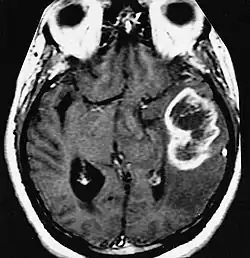

| An example of a ring-enhancement around a lesion in gliobastoma. In tumefactive multiple sclerosis, the ring-enhancement is open, not forming a complete ring. |

Diagnosis of tumefactive MS is commonly carried out using magnetic resonance imaging (MRI) and proton MR spectroscopy (H-MRS). Diagnosis is difficult as tumefactive MS may mimic the clinical and MRI characteristics of a glioma or a cerebral abscess. However, as compared to tumors and abscesses, tumefactive lesions have an open-ring enhancement as opposed to a complete ring enhancement.[1] Even with this information, multiple imaging technologies have to be used together with biochemical tests for accurate diagnosis of tumefactive MS.[36]